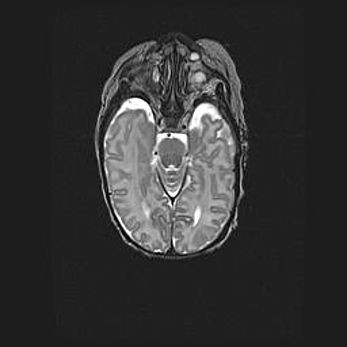

Множественные кисты обоих полушарий головного мозга, наибольшая из них в правой затылочной области. Ассиметричная атрофическая гидроцефалия.

Возраст: 7 месяцев

Вес: 5660 г

Пол: мужской

Окружность головы: 41,5 см

Срок гестации: 28-29 недель

Кисты головного мозга развиваются в результате многоочаговых некрозов вещества мозга и возникают вследствие перенесенной перинатальной инфекции, менингитов, энцефалитов, асфиксии, родовой травмы, расстройств мозгового кровообращения различного генеза. Образованию кист в веществе головного мозга плодов и новорожденных способствуют такие факторы, как высокое содержание в нем воды, недостаточная (или отсутствие) миелинизация и слабая астроглиальная реакция на повреждение.

Кисты могут сочетаться с гидроцефалией и другими поражениями головного мозга.